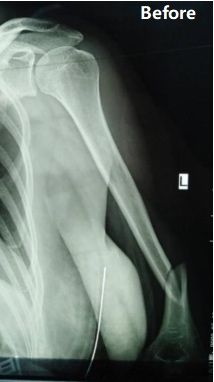

Panoramica del caso: a una paziente di 48 anni è stata diagnosticata la frattura del terzo medio-distale dell'albero omerale sinistro (classificazione AO: tipo B1).